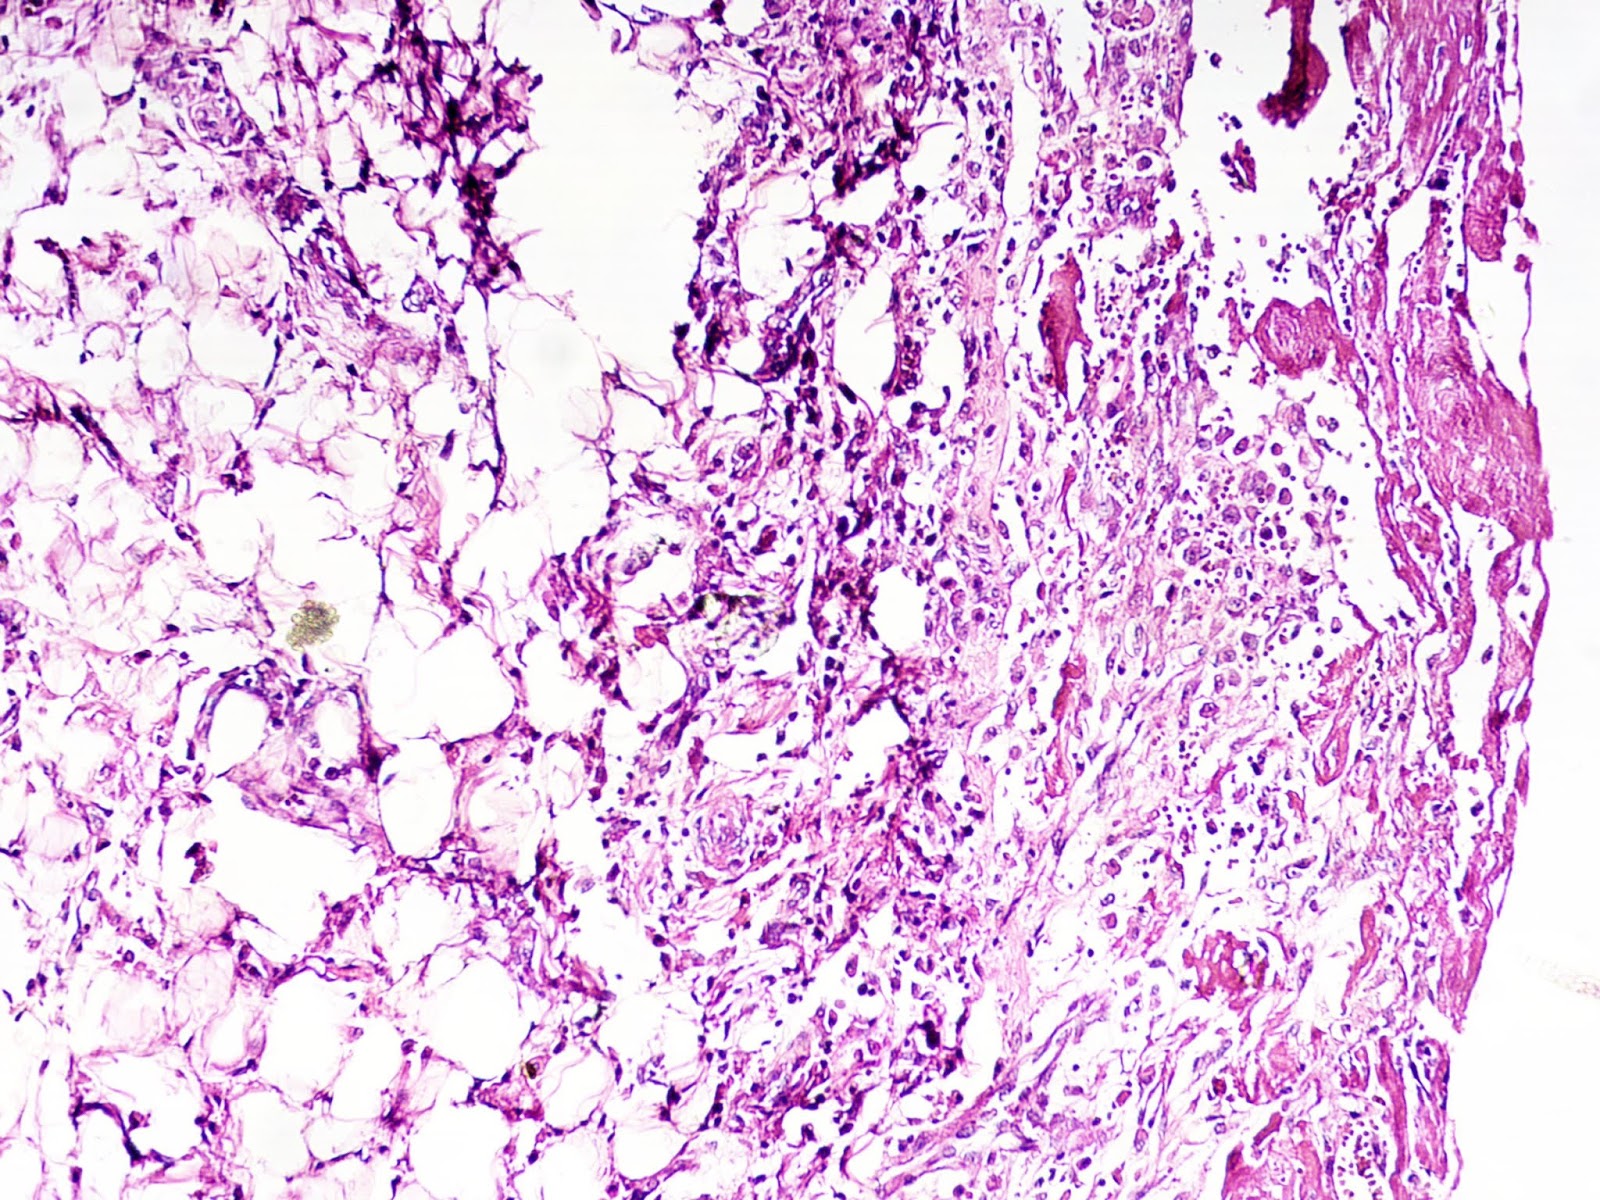

Bread And Butter Pericarditis Means . Pericarditis, also known as “bread and butter” pericarditis.7 in such an entity, the pericardium, which is regularly smooth and bright, becomes. This is another example of fibrinous pericarditis. Pericarditis is the inflammatory process involving the pericardium as a result of a systemic disease or a primary pericardium. There are a number of possible causes of acute fibrinous pericarditis,. The cause in this case is unknown. This is an example of acute fibrinous (bread and butter) pericarditis. The epicardial surface of the heart shows a shaggy fibrinous exudate.

Pericarditis, also known as “bread and butter” pericarditis.7 in such an entity, the pericardium, which is regularly smooth and bright, becomes. This is another example of fibrinous pericarditis. The epicardial surface of the heart shows a shaggy fibrinous exudate. The cause in this case is unknown. This is an example of acute fibrinous (bread and butter) pericarditis. Pericarditis is the inflammatory process involving the pericardium as a result of a systemic disease or a primary pericardium. There are a number of possible causes of acute fibrinous pericarditis,.